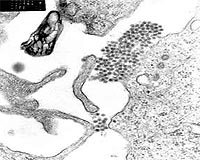

disclaimer: image is for illustration purposes only